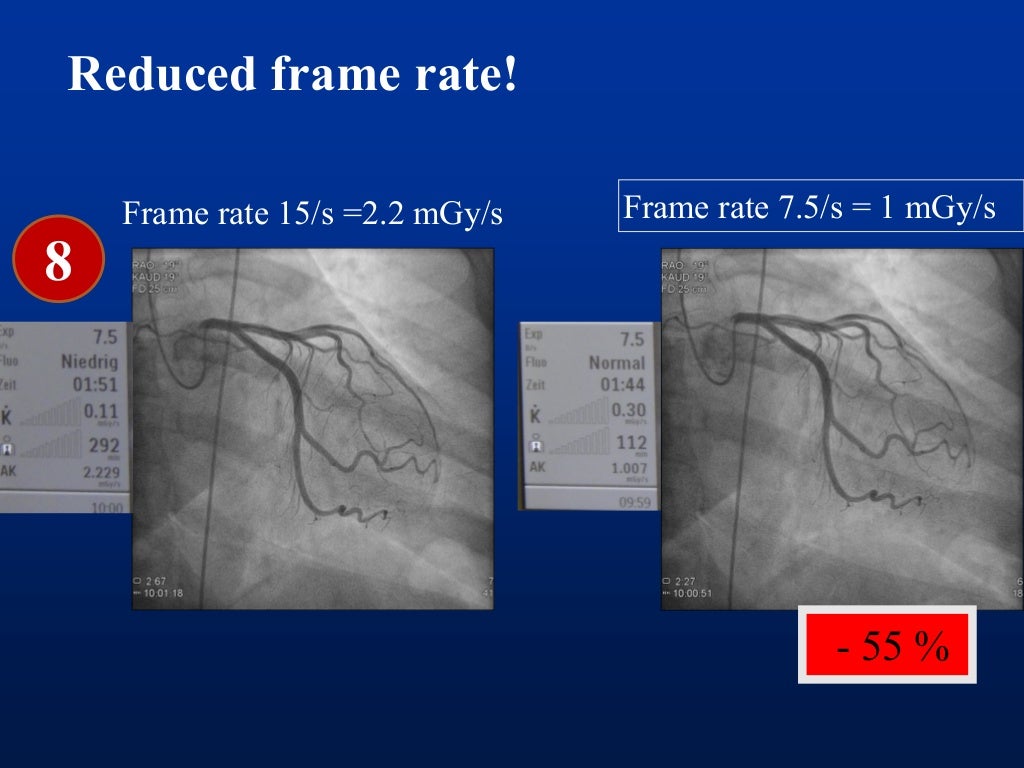

I) use collimator to set minimal useful field size, keep image intensifier in close proximity.

This principle confers to physicians the responsibility for reducing as much as possible the dose of radiation during cardiovascular procedures to minimize the. Radiation exposure can be accumulated over the time of. We strive to perform only tests that are necessary and to use just enough radiation doses to provide a high quality image to help your.

There are various types of shielding used in the reduction of radiation exposure including lead aprons, mobile lead shields, lead glasses, and lead barriers. The purpose of this article is to (a) describe the importance of educating radiology personnel, patients, and referring clinicians about the concerns over ct radiation, (b). Every diagnostic medical procedure involving ionizing radiation needs to minimize radiation exposure without compromising the benefit for the patient.

Steps we take to minimize radiation. Time, distance, and shielding measures minimize your exposure to radiation in much the same way as they would to protect you against overexposure to. Time, distance, and shielding actions minimize your exposure to radiation in much the same way as they would to protect you against overexposure to the sun: